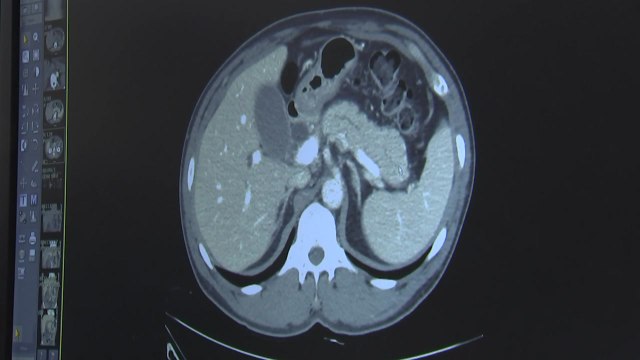

[앵커] 췌장암은 흔히 '침묵의 살인자'로 불립니다. 조기 발견이 어려워 증세를 느꼈을 때는 이미 치료 시기를 놓치는 경우가 많기 때문인데 현재로썬 예방이 최선의 방책이라고 합니다. 이양현 기자의 보도입니다. [기자] 생존율이 80-90%를 웃도는 위암이나 대장암 등과 달리 췌장암은 수십 년 동안 생존율이 정체되어 있는 유일한 질환입니다. 췌장은 몸속 깊은 곳에 위치하기 때문에 발견이 어려워 암 진단을 받은 경우 생존율이 5%에 불과합니다. 췌장암은 배 부위나 등이 답답하다거나 속이 안 좋은 정도로 여러 질환에서 공통적으로 나타나는 증세를 보여 대수롭지 않게 여기기 쉽습니다. 통증이 없는 황달이 나타나거나 몸이 가렵고 소변의 색이 진해지는 증상이 나타나기도 합니다. 이럴 경우 초음파검사로 담관, 담낭,췌장을 관찰하고 CT나 MRI 등으로 세밀히 검사해야 합니다. 하지만 췌장암은 발견하기가 쉽지 않고 진단 시 치료 가능성이 낮은 만큼 예방이 가장 중요하다고 전문가들은 조언합니다. 췌장암을 발생시키는 주요 요인으로는 40대 이상의 연령층과 흡연 경력 그리고 고지방, 고열량 음식 섭취 등이 꼽히고 있습니다. 특히 췌장암 환자 중 가족력이 있는 경우가 약 7.8%로 일반이 췌장암 발생률 0.6%보다 훨씬 높아 가족 가운데 췌장암 환자가 있는 경우 각별한 주의가 요망됩니다. YTN 이양현입니다. ▶ 기사 원문 : ytn.co.kr/_ln/0103_201705040459417433 ▶ 제보 안내 : goo.gl/gEvsAL, 모바일앱, [email protected], #2424 ▣ YTN 유튜브 채널 구독 : goo.gl/Ytb5SZ [ 한국 뉴스 채널 와이티엔 / Korea News Channel YTN ] Рекомендуем '침묵의 살인자' 췌장암, 예방이 중요하다! / YTN посмотреть онлайн видео бесплатно и без регистрации!